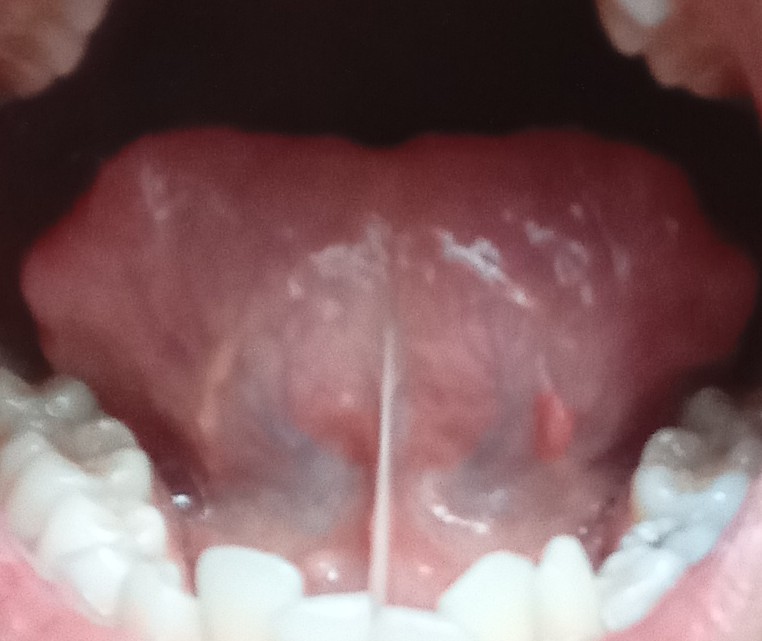

เจ็บใต้ลิ้น อาการนี้คืออะไร

ขออภัยในรูปที่ไม่สวยงาม แต่มีอาการเจ็บในช่องปากเลยอยากทราบว่า บริเวณใต้ลิ้นฝั่งขวาจะมีติ่งเล็กๆ เกี่ยวออกมาจากเส้นใต้ลิ้น มีอาการปวมแดงและเจ็บเวลาจับหรือขยับลิ้น มีการห้อเลือด เลยอยากทราบว่ามีใครเคยเป็นหรือมีวิธีลดอาการอย่างไรบ้าง และอยากทราบว่ามันเกิดจากอะไรได้